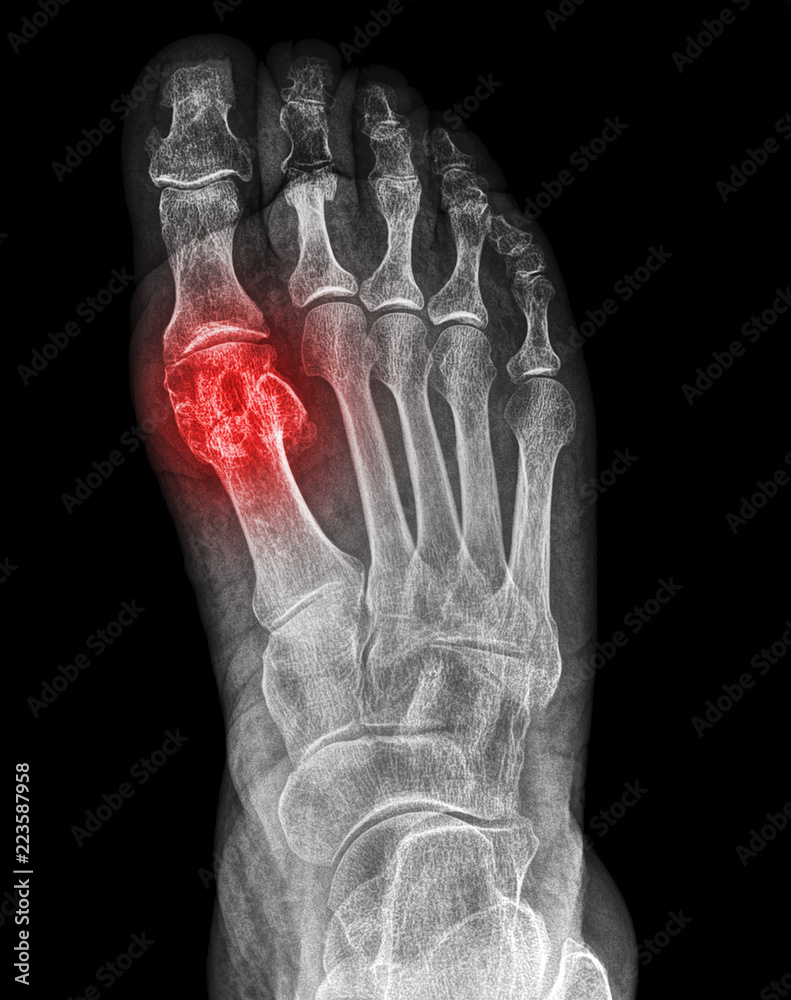

an xray of a human metatarsal bone fracture, diagnosis, broken Stock Closed Fracture Of Metatarsal Bone Icd 10 S92.301a.… initial encounter for closed fracture. The main goal of treatment is to restore the alignment of all metatarsals, hence. Metatarsal fractures are relatively common injuries of the foot. S92.302a is a billable diagnosis code used to specify a medical diagnosis of fracture of unspecified metatarsal bone(s), left foot, initial. Fracture of unspecified metatarsal bone (s), right foot, initial encounter. Closed Fracture Of Metatarsal Bone Icd 10.

Xray fracture of the first metatarsal bone Stock Photo Adobe Stock Closed Fracture Of Metatarsal Bone Icd 10 S92.302a is a billable diagnosis code used to specify a medical diagnosis of fracture of unspecified metatarsal bone(s), left foot, initial. The icd code s923 is used to code jones fracture. Use s92.313a for initial encounter for closed. Metatarsal fractures are relatively common injuries of the foot. S92.301a.… initial encounter for closed fracture. Fracture of unspecified metatarsal bone (s), right. Closed Fracture Of Metatarsal Bone Icd 10.